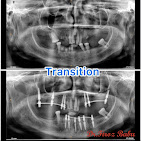

• Dental Implants & Full Mouth Implants: Permanent solutions for missing teeth, including advanced Zygomatic Implants for patients with bone loss.